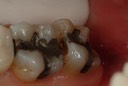

Mark Chun #31 pre-op

Mark Chun #31 amalgam removal